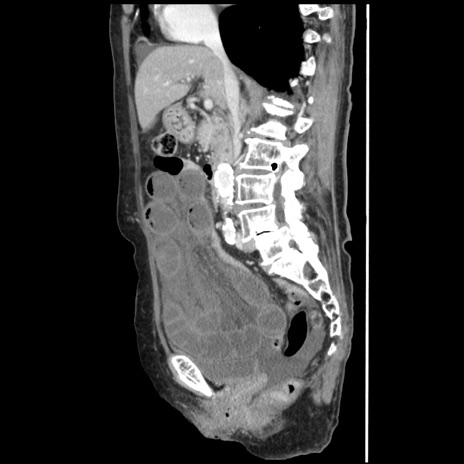

症例1(矢状断像)

【症例】80歳代女性

【主訴】腹痛

【現病歴】8時間前から腹痛あり来院。

【既往歴】糖尿病、脂質異常症、子宮体癌にて子宮全摘術

【身体所見】意識清明・会話良好だが腹痛で苦悶様、全腹部にわたって反跳痛と圧痛あり

【データ】WBC 13600、CRP 0.14、LDH 224、CK 90